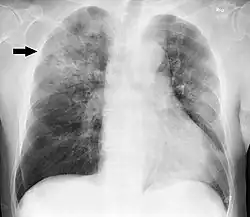

A chest radiograph is frequently used in diagnosis.[23] In people with mild disease, imaging is needed only in those with potential complications, those not having improved with treatment, or those in which the cause is uncertain.[23][69] If a person is sufficiently sick to require hospitalization, a chest radiograph is recommended.[69] Findings do not always match the severity of disease and do not reliably separate between bacterial and viral infection.[23]

X-ray presentations of pneumonia may be classified as lobar pneumonia, bronchopneumonia, lobular pneumonia, and interstitial pneumonia.[75] Bacterial, community-acquired pneumonia classically show lung consolidation of one lung segmental lobe, which is known as lobar pneumonia.[42] However, findings may vary, and other patterns are common in other types of pneumonia.[42] Aspiration pneumonia may present with bilateral opacities primarily in the bases of the lungs and on the right side.[42] Radiographs of viral pneumonia may appear normal, appear hyper-inflated, have bilateral patchy areas, or present similar to bacterial pneumonia with lobar consolidation.[42] Radiologic findings may not be present in the early stages of the disease, especially in the presence of dehydration, or may be difficult to interpret in the obese or those with a history of lung disease.[24] Complications such as pleural effusion may also be found on chest radiographs. Laterolateral chest radiographs can increase the diagnostic accuracy of lung consolidation and pleural effusion.[41]